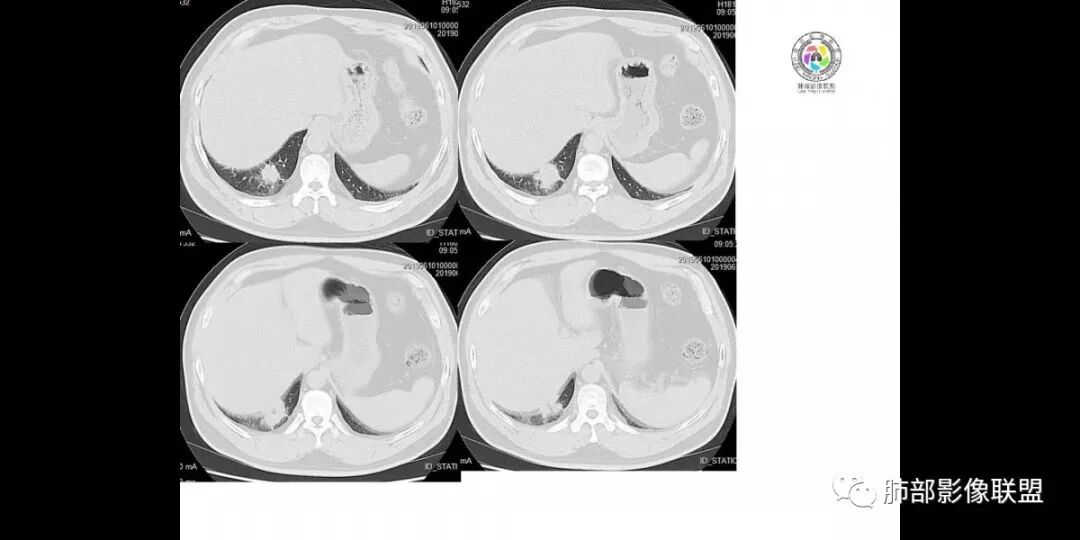

患者男,45岁,因乏力、低热、心悸入院,最高体温38℃,偶有咳嗽、无咳痰、咯血,肿瘤标志物阴性。

影像资料

右肺下叶后基底段胸膜下肿块,边缘平直、凹陷为主, 局部膨隆 ,周围模糊毛玻璃影及锁条, 内见坏死,明显强化,较均匀,下缘糊墙,考虑炎性,慢性脓肿?鉴别炎性合并肿瘤。

中年男性,乏力  低热入院,胸CT:右肺下叶后基底段结节样病变,病灶周围可见细支气管扩张,病灶边缘可见短软毛刺,病灶周围有毛玻璃影,冠状位肺窗病灶与膈胸膜呈宽基地,纵隔窗可见病灶内空洞及低密度区,增强明显强化及延迟强化,考虑良性感染性病变,隐球菌肺炎?,结核?。但在冠状位肺窗有一支细支气管在病灶旁有截断,还得除外肺癌的可能性。

男,45岁;乏力、低热、心悸,38°,偶咳;症状像结核,但无钙化,无积液;三期:35-57-71偏心空洞,冠状位胸膜有牵拉力:需考虑鳞癌,男性,45岁,年龄偏小,吸烟史?

患者中年男性,以乏力、低热、心悸入院。胸部CT:右肺下叶后基底段近胸膜实性结节灶,病灶周围磨玻璃模糊影,可见短毛刺,边缘呈刀切、平直,冠状位肺窗病灶与膈胸膜呈宽基地,纵隔窗可见病灶内空洞及低密度区,增强明显强化及延迟强化,综合考虑良性感染性病变。肺隐球菌病可能大,机化性肺炎、腺癌次之,结核待排。

右肺下叶后基底段结节,边缘较清,有浅分叶,病灶长轴与胸膜平形,以平直收缩为主,局部稍膨隆,有长短不一的毛刺,边缘模糊,周围有小片状模糊hggo,中心有小空泡或小空 洞,内壁光整,增强后延迟强化,提示会不会有纤维组织成份,而且空腔内壁强化明显且完整,邻近胸膜有糊墙,考虑炎性病变,机化性肺炎合并脓肿?鉴别癌。

机化性肺炎(炎性假瘤)

病理学特征:机化结节形成(梭形纤维母细胞和肌纤维母细胞位于浅染的间质中),机化结节位于肺泡腔、肺泡囊和终末细支气管内,周围间质有炎性细胞浸润。缺乏坏死、缺乏肉芽肿、缺乏明显嗜酸性粒细胞浸润。肺结构常完整。

5.病灶密度均匀,偶见空洞及钙化。强化较明显且持续,均匀或不均匀。